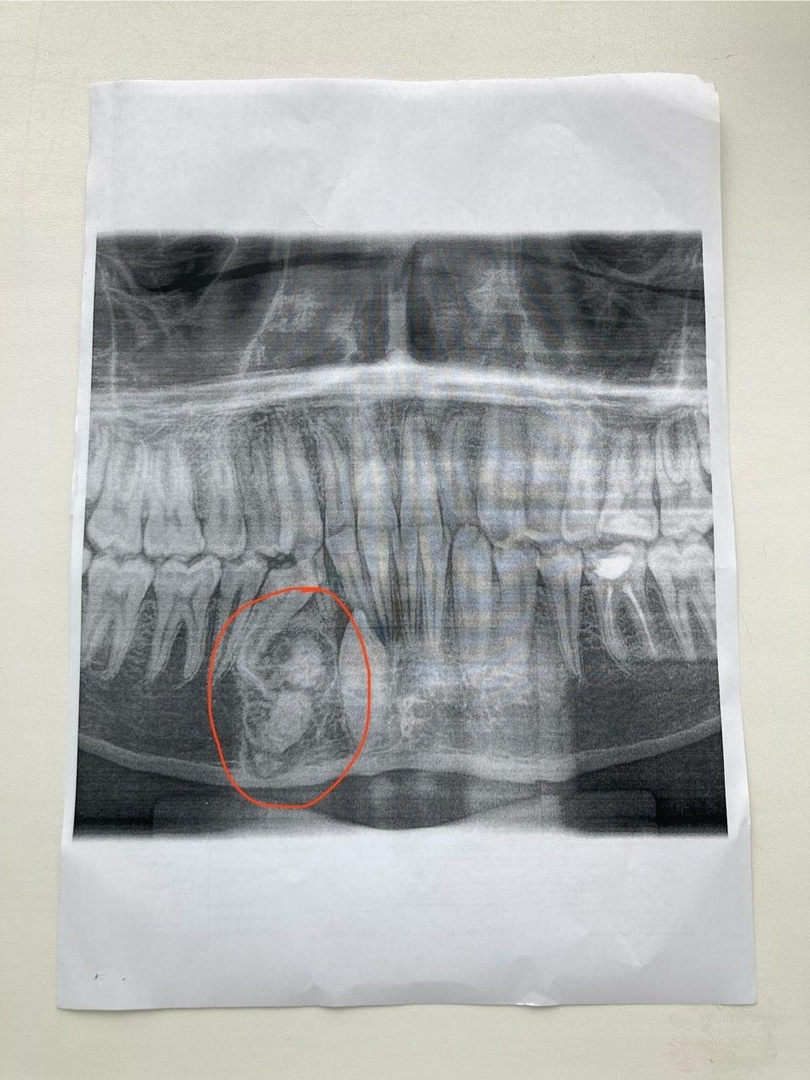

В одном из медицинских учреждений ОДКБ был зарегистрирован редкий случай, когда у ребенка на нижней челюсти выросло более 30 лишних зубов. Челюстно-лицевой хирург Андрей Мухин провел сложную операцию по удалению всех избыточных зубов, которые образовались в опухоли на нижней челюсти.

Как сообщают специалисты ОДКБ, обычно в ротовой полости у человека может вырастать 1-2 лишних зуба, чаще всего это передние зубы верхней челюсти, но в данном случае произошло нечто необычное. Состояние, наблюдаемое у этого пациента, называется полиодонтия или гипердонтия, и по статистике оно встречается примерно у 6% населения.

Однако бывают и более сложные случаи, как в этой ситуации, когда количество избыточных зубов оказывается крайне большим. Хирурги удалили более 30 зубов, которые были частью опухоли, что является настоящим медицинским вызовом.